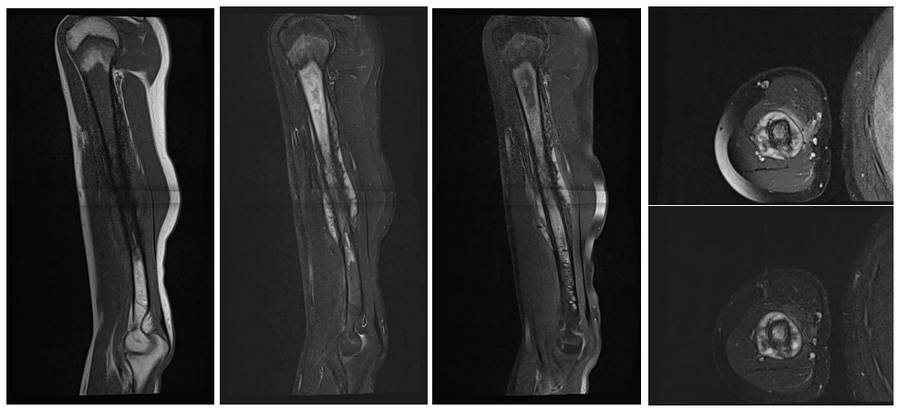

Ameliyat Öncesi: MR’da yumuşak doku komponenti ve çevreleyen ödem görülmekte